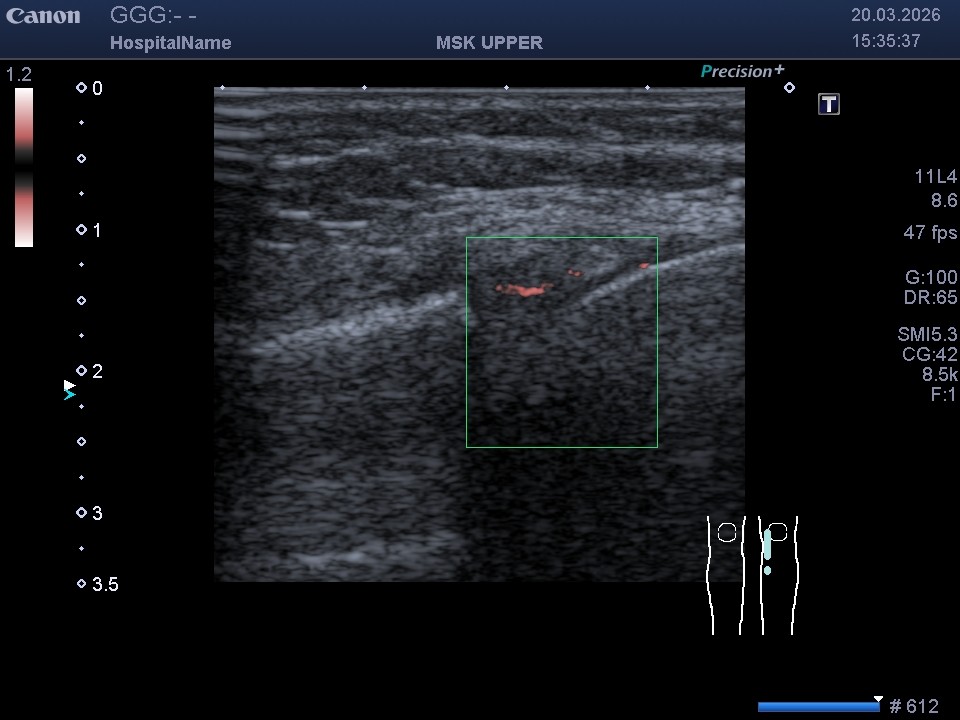

- Технологія SMI (візуалізація мікроциркуляторного русла): Це унікальний режим, що дозволяє побачити найдрібніші судини. Завдяки SMI ми можемо визначити кровопостачання «червоної зони» меніска та зафіксувати рідкісне явище — неоангіогенез (появу нових судин) у «білій зоні» після травми.

Розриви в червоній зоні (де є кровопостачання) загоюються набагато швидше. Біла зона позбавлена судин, тому відновлення там проходить важче. На звичайному УЗД (В-режимі) відрізнити ці зони неможливо, але режим SMI дозволяє відмежувати їх завдяки доплерівському сигналу від мікросудин.